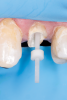

Fig 1. Example of the ferrule effect. The completed crown preparation should have a ferrule design, as shown, that encapsulates the endodontically restored tooth complex.

Figure 1

A modified interpretation is that parallel walls of dentin extending coronally from the crown margin provide a ferrule preparation design, which after being surrounded by a crown provides a protective mechanism against fracture by reducing stresses within the tooth; this is called the "ferrule effect."20,22 The ferrule design has also been described as incorporating a crown with a 360-degree collar that encompasses the perimeter of the prepared parallel dentin walls and extends cervically to the prepared tooth margin. This design improves the mechanical resistance of the treated tooth by distributing forces on the remaining tooth structure.24,29-31 Preserving tooth structure during preparation is paramount in preventing stress concentrations at the cementoenamel junction of the endodontically restored tooth and providing resistance to tooth fracture. Because maximum preservation of coronal and radicular tooth structure is imperative for optimizing biomechanical behavior of the restored tooth and the long-term survival of endodontically treated crowned teeth,20,32-34 the completed crown preparation should have a ferrule design that encapsulates the endodontically restored tooth complex (Figure 1). The objective of the ferrule is to enhance the structural integrity of the endodontically treated tooth by counteracting stresses such as functional lever forces, the wedging effect of tapered post systems, and lateral forces generated during post placement.9,14,24,35-38 Design parameters to consider for the effectiveness of the ferrule include: number of walls; ferrule width, height, and configuration; design of the cervical collar; type of tooth; the tooth's location in the oral cavity (ie, maxilla/mandible, anterior/posterior); occlusal forces; remaining wall parallelism; post design and material; core material and type; thickness of cement; and type of restoration.9,12,14,19,20,22,24,29-31,39-52